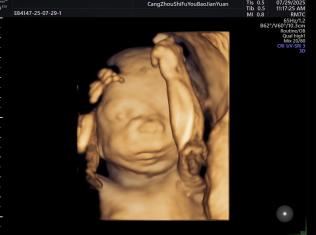

给宝宝的“立体影像”,让产检更安心

科室采用三维/四维超声技术开展胎儿检查,能清晰呈现胎儿面部及身体关键结构的影像,让准父母直观感受宝宝的发育状态。检查中,医生会借助技术对唇腭裂、小下颌等结构异常进行细致观察,同时基于三维容积数据,从多个平面评估胎儿心脏、大脑、脊柱等重要部位,为孕期健康管理提供专业参考。

四维诊断小下颌畸形